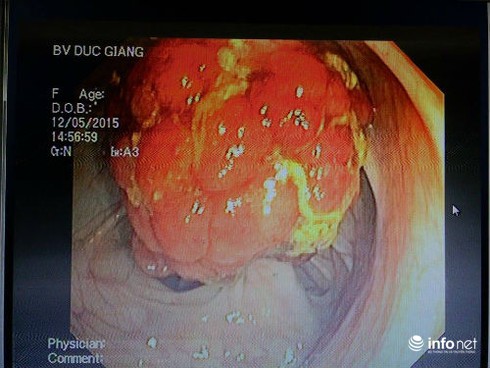

Hình ảnh khối polyp đại tràng của bệnh nhân T. |

Bác sĩ chuyên khoa I - Vũ Huy Hiền – Phó trưởng khoa phụ trách khoa Thăm dò chức năng Bệnh viện Đa khoa Đức Giang, Hà Nội cho biết bệnh viện vừa cắt một ca polyp đại tràng khủng có kích thước 2,5 cm – 3cm.

Đây là polyp lớn nhất mà Bệnh viện Đa khoa Đức Giang cắt đồng thời cũng là một trong những polyp to hiếm thấy.

Bệnh nhân là chị P.X.T 30 tuổi vào viện cấp cứu trong tình trạng đau bụng, đi ngoài ra máu. Qua nội soi, bác sĩ đã phát hiện bệnh nhân có khối polyp khá lớn. Sau can thiệp, sức khỏe bệnh nhân hồi phục tốt.

Nói về bệnh nhân này, bác sĩ Hiền cho biết các bác sĩ phải tiến hành kẹp chân polyp để cầm máu trước, sau đó mới cắt vì polyp to, nguy cơ chảy máu cao, bác sĩ phải tiến hành cắt làm 2 lần.